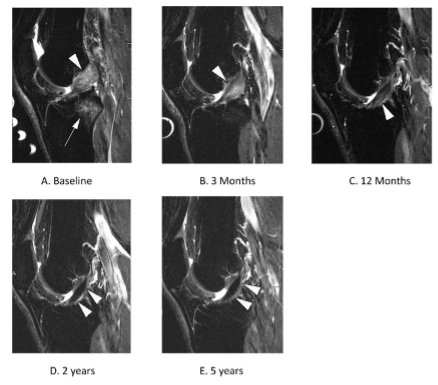

If you were to ask this question 20 years ago, the answer would be a resounding NO! Interestingly, as there has been further investigation into ACL recovery over the past couple of decades, there have been cases where the ACL has shown signs of healing on MRI.

Recently in a more rigorous study, researchers demonstrated ACL healing in 1/3 of their participants who underwent rehabilitation only. What’s even more interesting, is that these individuals had better outcomes and were less likely to request surgery compared to those who did not have any signs of healing. This suggests a potential explanation for why different people experience varying success with conservative management.

While we are now confident that the ACL can heal on its own, we have still yet to answer why it heals only in certain cases. One thought is that by reducing the distance between the two torn ends, we may be able to facilitate healing. A newly developed bracing protocol attempted to answer this question by immobilizing the knee in a bent position for 4 weeks. Remarkably, they reported that of the 80 people managed with this method, 90% had signs of healing on MRI. Although promising, more information is needed before we can confidently make any recommendations about this novel approach. Regardless, it is exciting that this maybe the new standard of care for ACL management in the future.

ACL healing demonstrated on MRI: Taken from Filbay et al., 2023